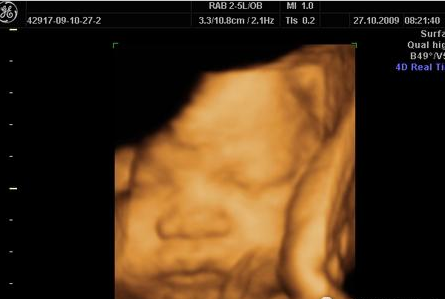

很多妊娠中的妇女都会通过四维彩超来鉴定胎儿的性别,健康情况,其实做四维彩超也是有很多讲究的,那么四维彩超什么时候做最好呢?...

现在很多准妈妈通过各种宣传都知道了有一种神奇的技术叫做“四维彩超”,它能够让准妈妈实现给宝宝拍摄“零岁写真”的愿望。但是什么时候做四维彩超才是最好的时间?...

告诉我,你们选择了四维彩超吗?在选择之前,准妈们真的有做好功课吗?相信每个准妈说起彩超排畸都可以说得头头是道,但对于四维彩超的“真面目”你们到底了解多少?...

二维彩超,三维彩超,四维彩超……相信每个准妈妈准爸爸对这些孕期检查项目都不陌生。因为在孕20~24周时,医生们都会提醒妈妈们去做一个大排畸的检查。...